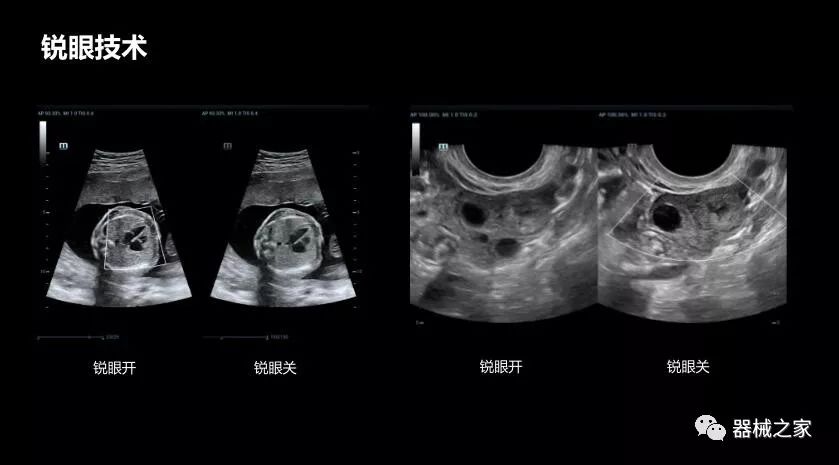

銳眼技術(shù)

做胎兒心臟檢查的時(shí)候,如果是聲窗不好的孕婦,很難看清胎兒心腔 。女?huà)zResona 8的銳眼技術(shù)能很好的優(yōu)化心腔內(nèi)的噪聲,讓胎心結(jié)構(gòu)完美的呈現(xiàn)。